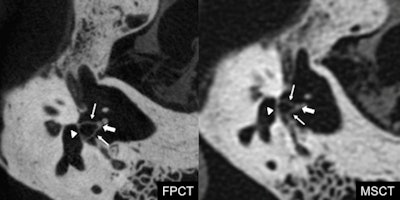

Clear results

While MDCT yielded higher signal, lower noise, higher signal-to-noise ratio (SNR), and fewer artifacts, flat-panel CT showed a significantly higher image quality overall score compared with MDCT (p < 0.0017 after application of the Bonferroni correction for multiple testing). Specifically, FPCT provided better images of 10 structures: the bone marrow of the malleus, the incudomalleolar joint, the anterior crus of the stapes, the posterior crus of the stapes, the footplate of the stapes, the tendon of the tensor tympani muscle, the stapedius muscle, the lateral ligament of the malleus, the modiolus, and the greater petrosal nerve (all p < 0.0017 after application of the Bonferroni correction for multiple testing). Furthermore, no structure was depicted better with MDCT than with flat-panel CT.